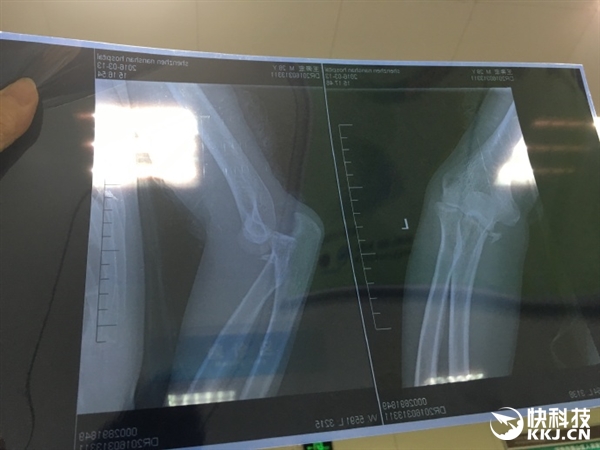

日前,微博網(wǎng)友@王奔宏 發(fā)帖稱(chēng),人生的第一次住院獻(xiàn)給了小米平衡車(chē)”,并展示了自己的住院證明和骨折拍片。

剛剛,@王奔宏 再次發(fā)微博稱(chēng):“為了避免給小米和納恩博產(chǎn)生不必要的負(fù)面影響,這里澄清一下事故過(guò)程,當(dāng)時(shí)的確下了點(diǎn)小雨,路面有些濕滑,但我車(chē)速并不快,平衡車(chē)行駛到瓷磚地面后其中一個(gè)輪子突然打滑,于是我便失去平衡重摔在地面上,因?yàn)樽笫窒乱庾R(shí)里進(jìn)行了支撐,所以致使左側(cè)尺骨冠突粉碎性骨折。”